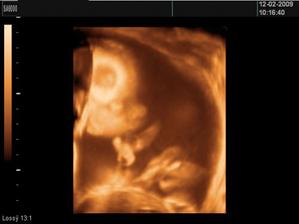

• 4.2.2009 - máme za sebou prvý 3D UTZ a už vieme že drobček bude EMILKO!!!